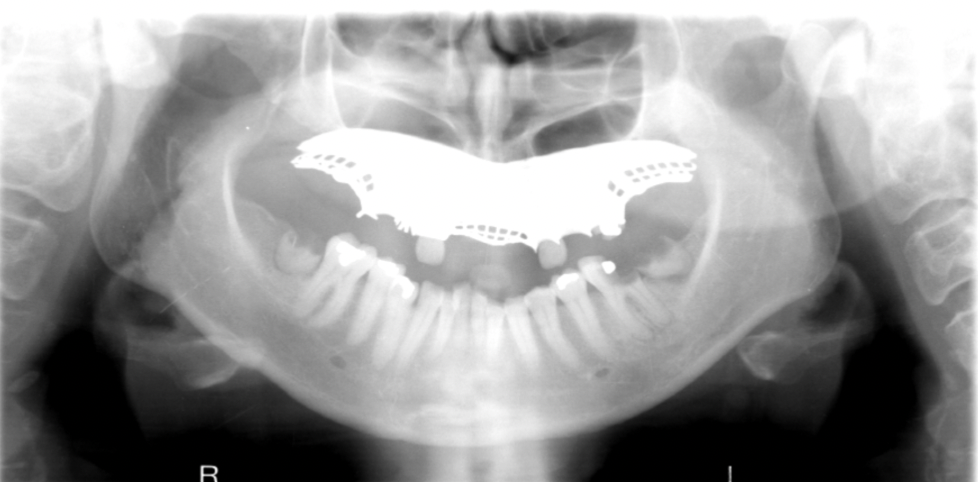

What are the errors in this radiographs? What is the cause of these errors?

A

1. anterior teeth widened & blurred

2. inferior tubercles and meati spread across maxillary sinuses

3. condyles are close to or cut off side image

Cause: Pt too far back